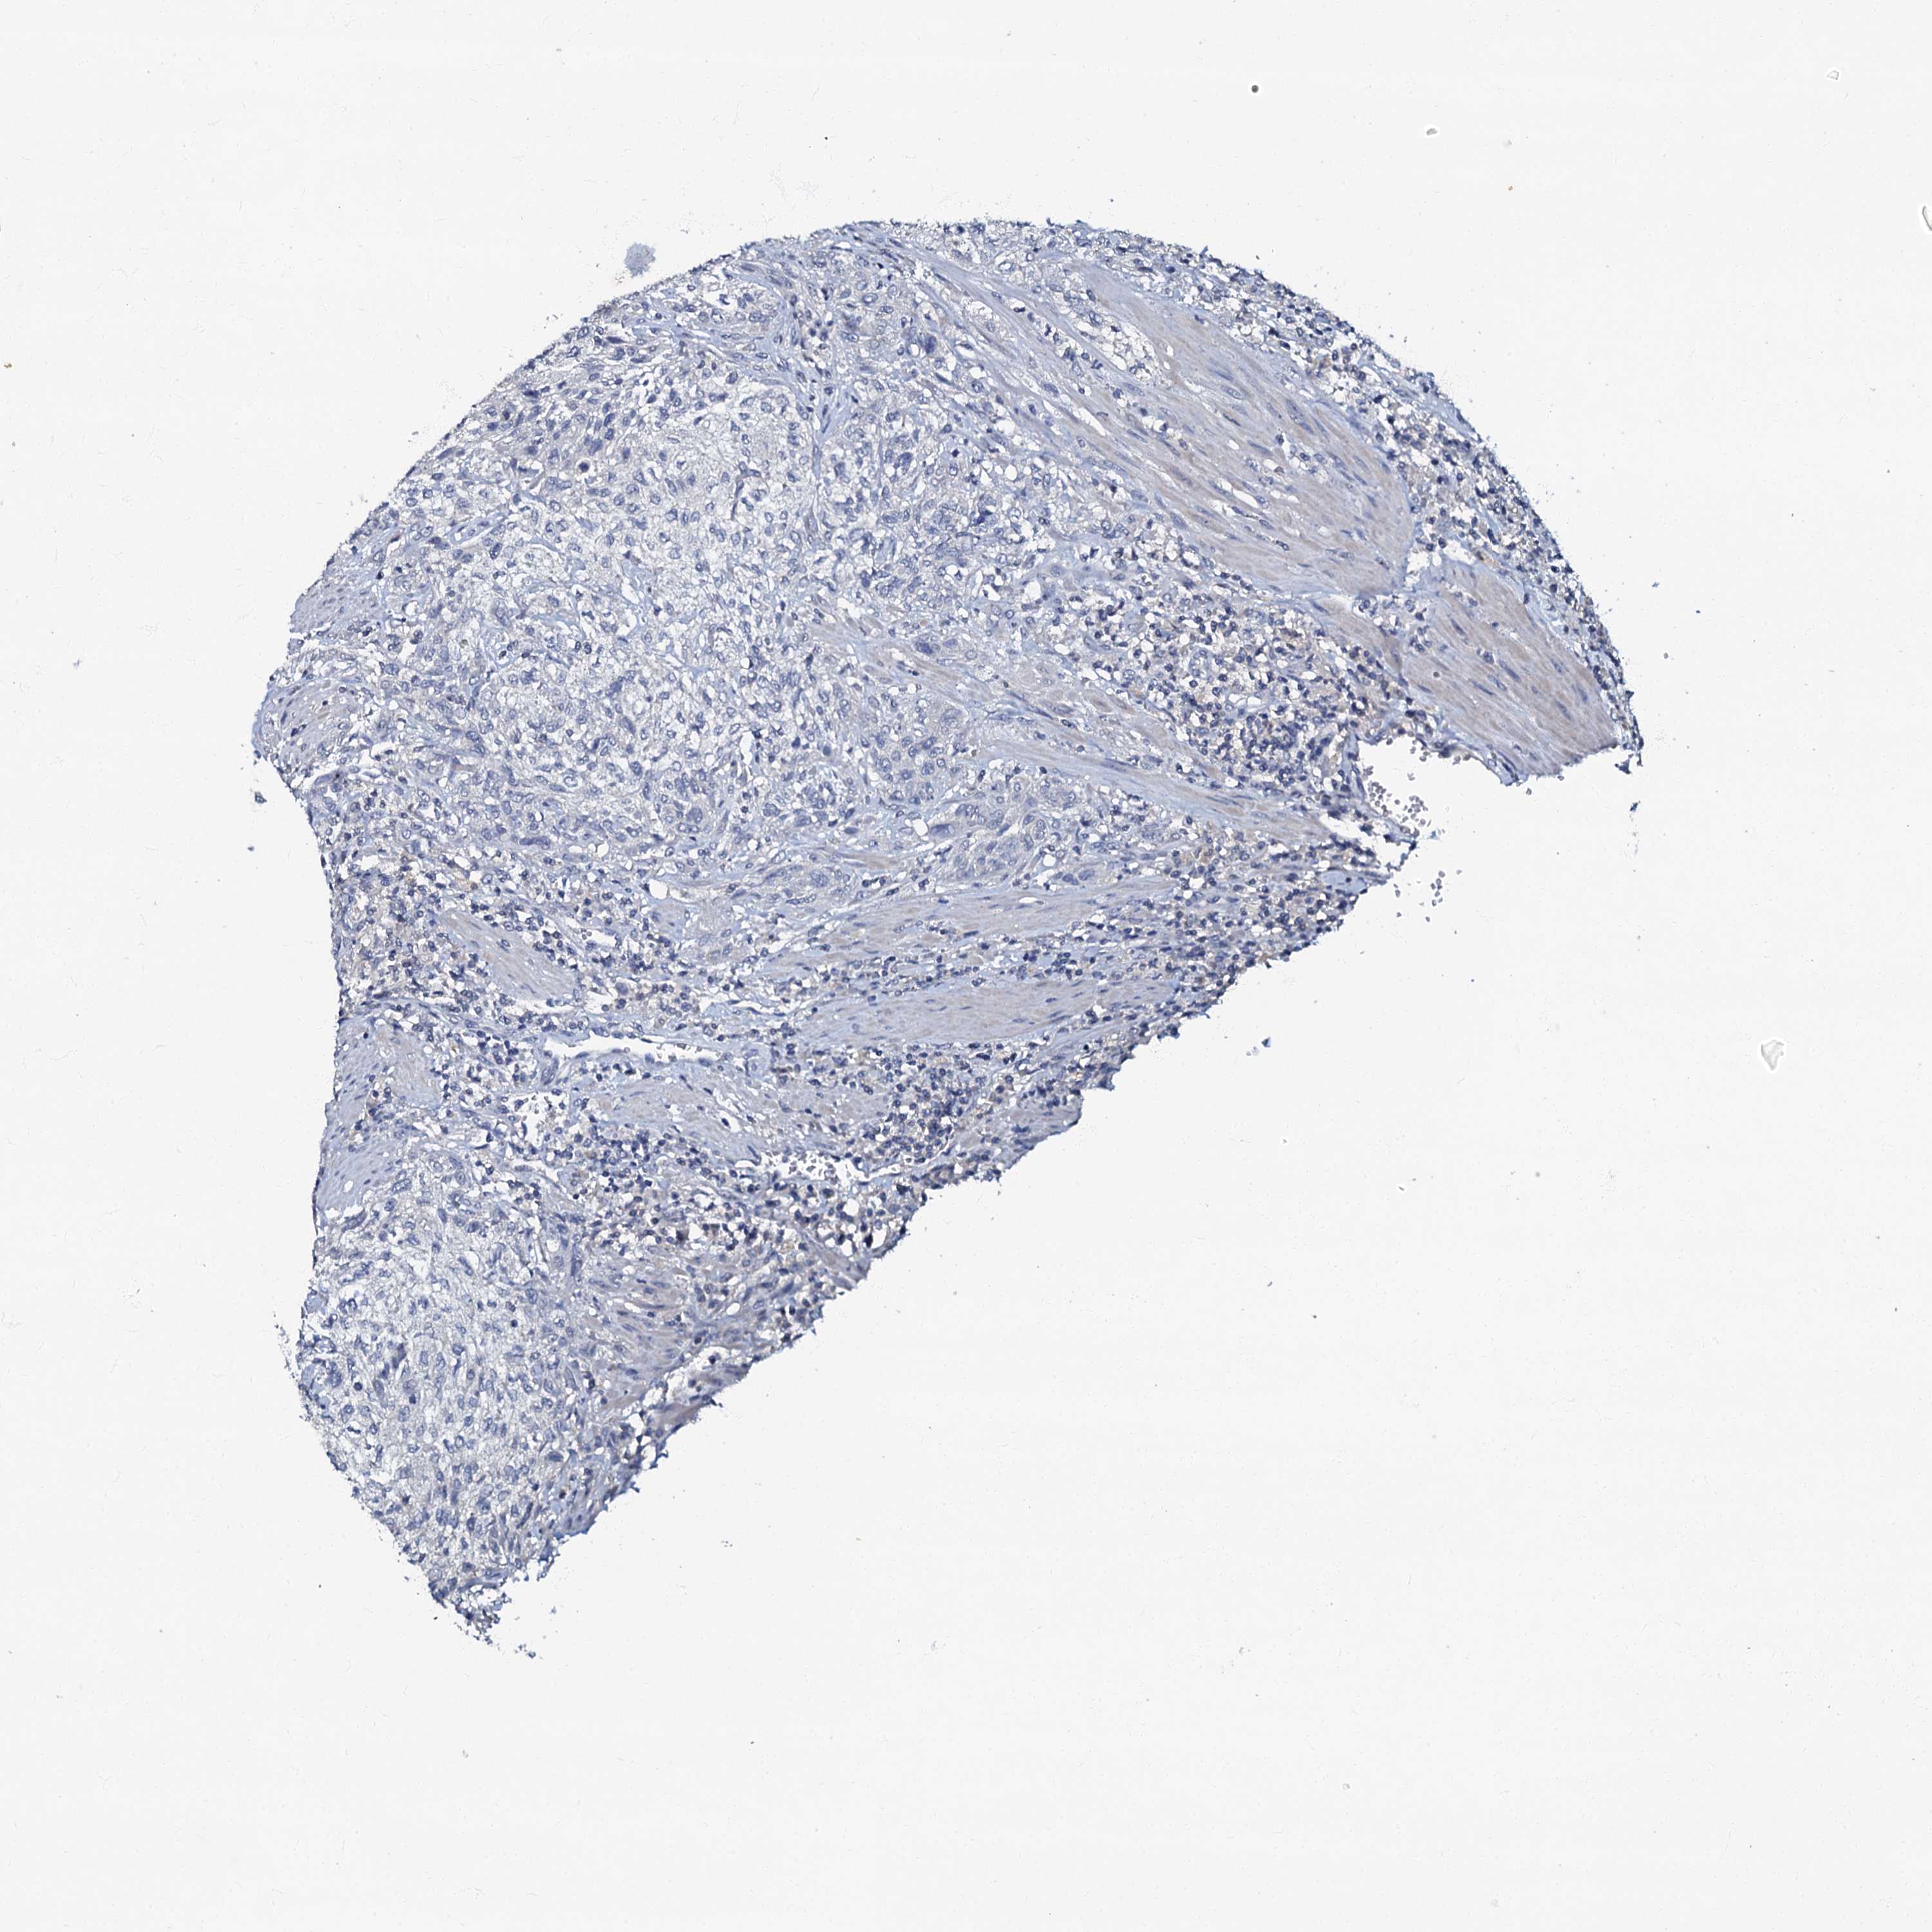

UROTHELIAL CANCER - Protein expressioni

A mouse-over function shows sample information and annotation data. Click on an image to view it in a full screen mode. Samples can be filtered based on level of antibody staining by selecting one or several of the following categories: high, medium, low and not detected. The assay and annotation is described here.

Antibody stainingi

Antibody staining in the annotated cell types in the current human tissue is reported as not detected, low, medium, or high, based on conventional immunohistochemistry profiling in selected tissues. This score is based on the combination of the staining intensity and fraction of stained cells.

Each image is clickable and will lead to virtual microscopy that enables deeper exploration of all samples and also displays staining intensity scores, fraction scores and subcellular localization as well as patient and tissue information for each sample.

Antibody HPA037947

Antibody HPA037948

Urothelial carcinoma, High grade

Urothelial carcinoma, Low grade

Urothelial carcinoma, NOS